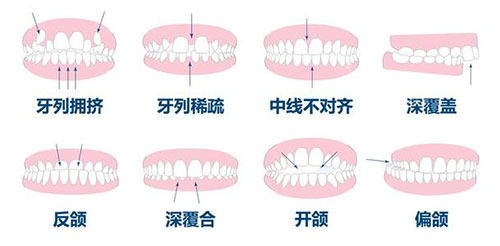

MBT 托槽适用于多种牙齿畸形,尤其是那些需要复杂矫正的患者。它的粘接技术简单,就像搭积木一样轻松,且舒适度高,患者在佩戴的时候更容易适应,仿佛牙齿在不知不觉中就变整齐了。

Roth 托槽更适用于需要拔牙矫正的病例,因为其转矩成效更佳,能够精密地控制牙齿的移动。然而,由于设计复杂,其适用人群相对更小。